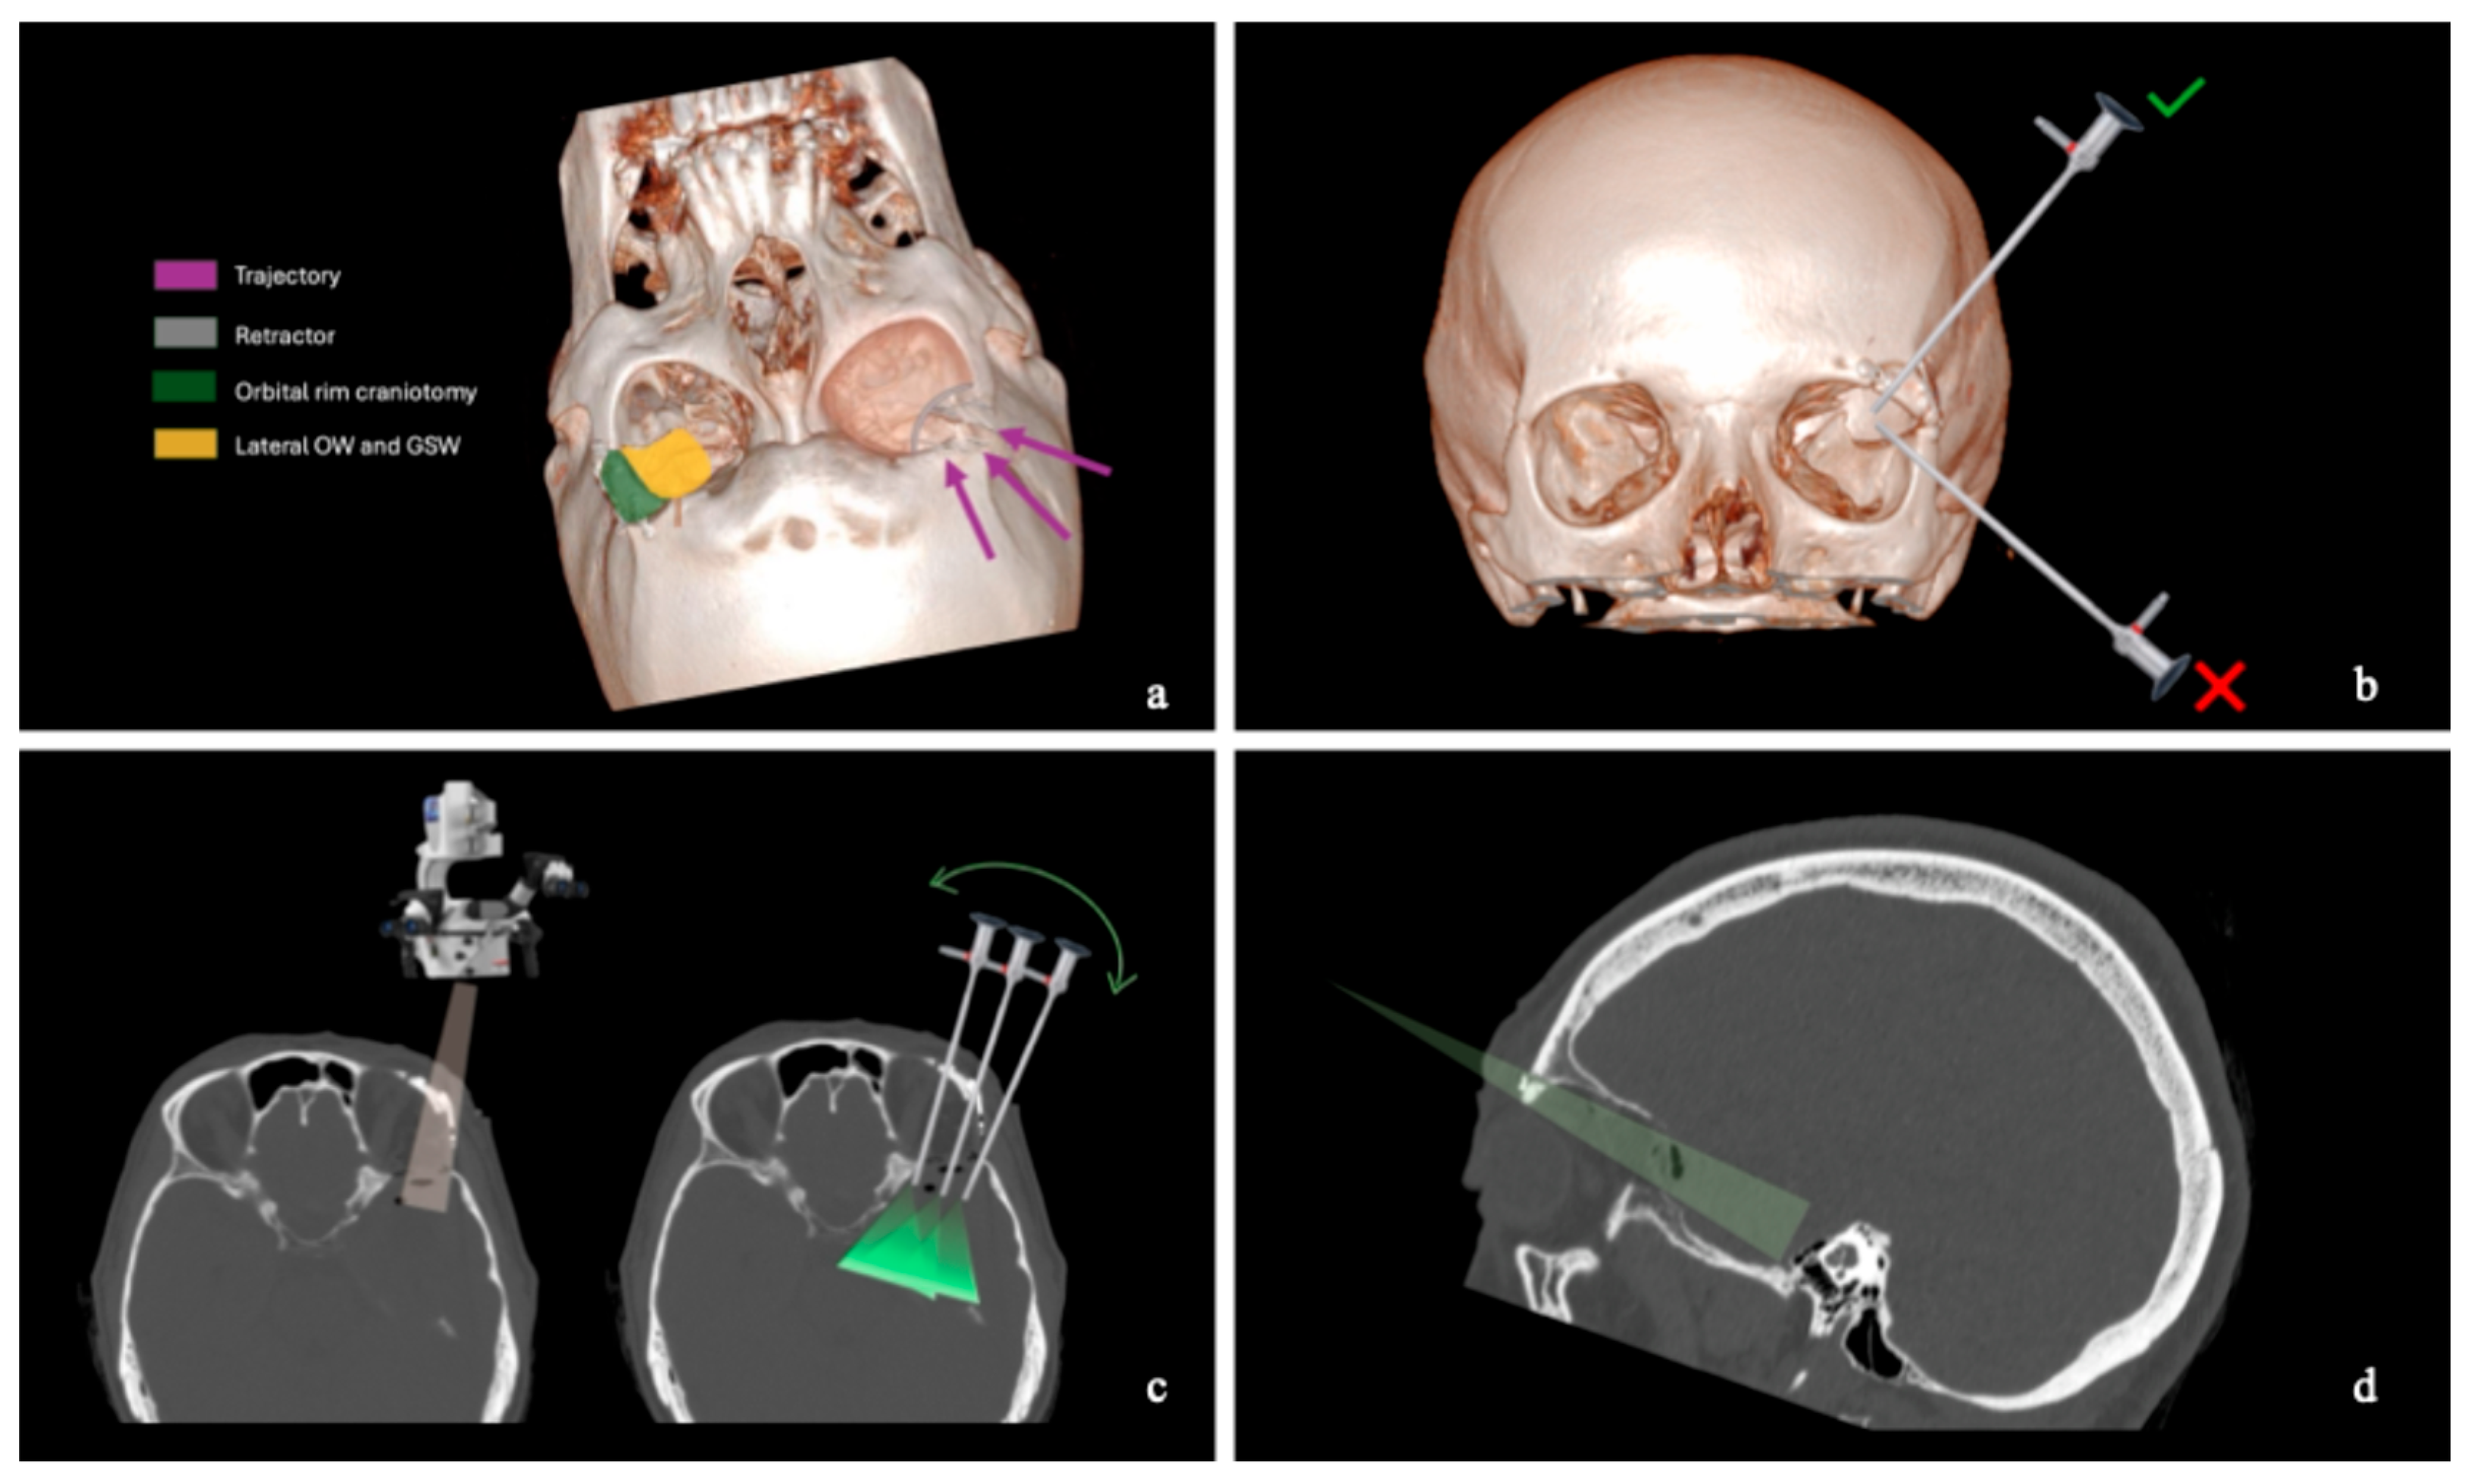

2.2. Skin and Craniotomy

2.3. Bony Phase

2.4. Extradural and Intradural Phases